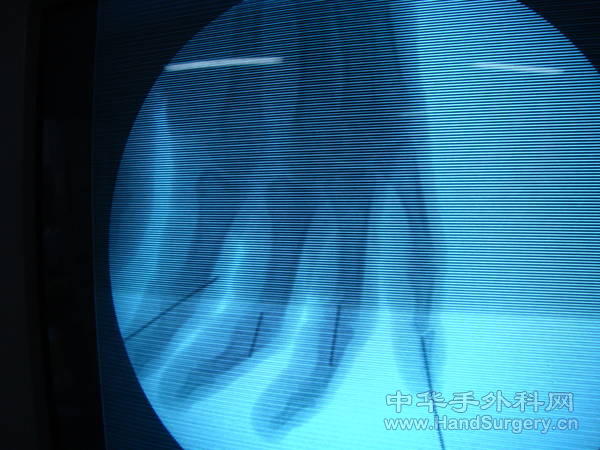

患者  男 32岁  绞伤至2-4指近指间关节开放脱位  急诊行脱位复位内固术、侧副韧带修补术,血管神经肌腱探查修补术,术后克氏针固定4周,功能锻炼历时2.5月。

术中复位关节后  常规修补两侧侧副韧带 及掌板   关节囊用5个0微翘线修补   术后十天后主动活动远指间关节  4周后拆除克氏针  配合中药熏洗功能锻炼